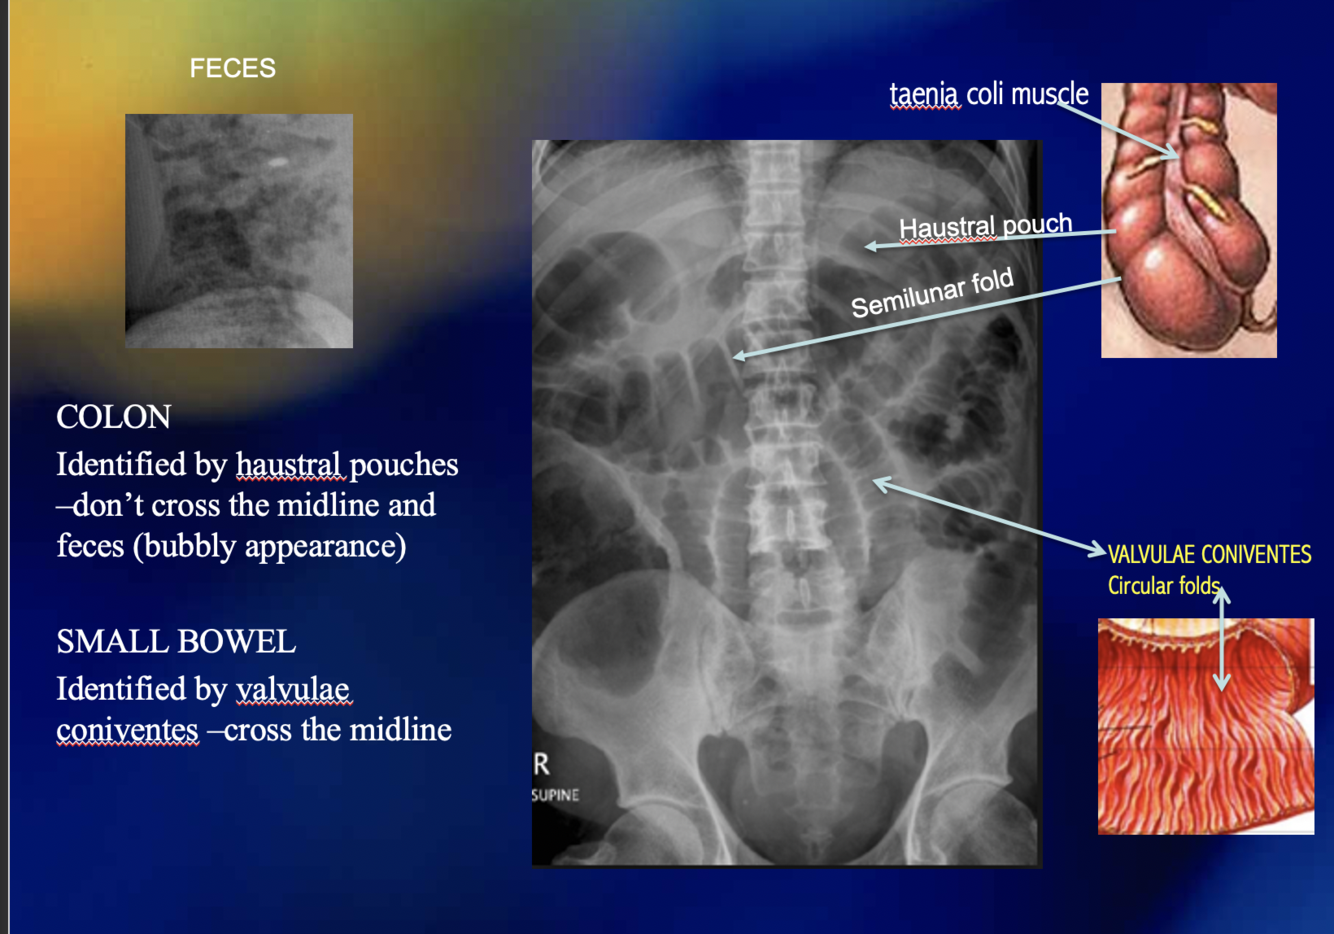

How can you differentiate between the small and large intestines in xray?

What is the “rule of 3s” with regards to a normal xray of the small bowel?